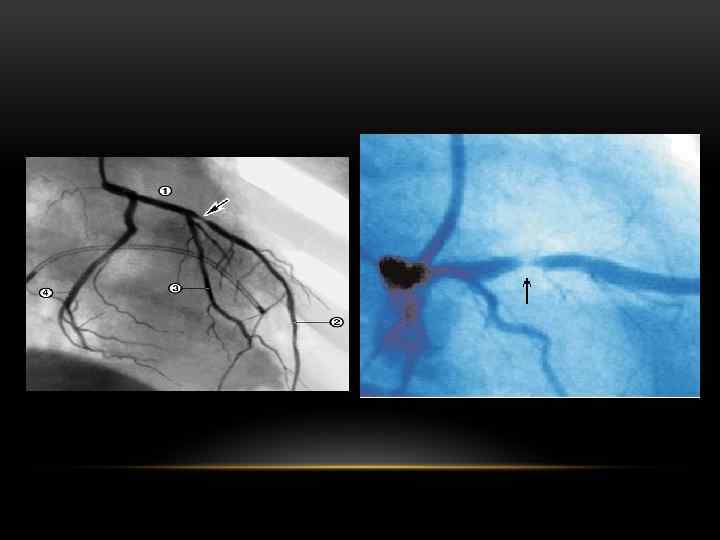

АНАТОМИЯ ВЕНЕЧНЫХ СОСУДОВ

ОЦЕНКА СТЕПЕНИ ВОССТАНОВЛЕНИЯ КРОВОТОКА ПО ДАННЫМ КОРОНАРОГРАФИИ Степень Данные коронарографии 0 Отсутствие кровотока: контрастное вещество не проходит ниже места закупорки 1 Минимальный кровоток: контрастное вещество просачивается ниже места закупорки коронарного сосуда, но не заполняет сосудистого русла 2 Частичный кровоток: контрастное вещество проходит ниже места окклюзии и заполняет сосудистое русло, однако медленнее, чем в нормальных сосудах 3 Полное восстановление кровотока: контрастное вещество заполняет сосуд ниже места закупорки так же быстро, как это происходит выше места окклюзии, контраст быстро покидает сосуд

АНГИОПЛАСТИКА ПРИ ОСТРЫХ КОРОНАРНЫХ СИНДРОМАХ • Первичная ( «прямая» ): проводится больному без предварительной тромболитической терапии. • Вторичная: ранняя (спасительная) - выполняется в остром периоде ИМ с целью восстановления коронарного кровотока при неэффективности тромболизиса, при наличии кардиогенного шока у больных моложе 75 лет, при СН Killip III, желудочковых аритмиях; отсроченная - выполняется после купирования острых явлений ишемии миокарда у больных высокого риска по данным неинвазивных тестов и у больных с постинфарктной стенокардией.